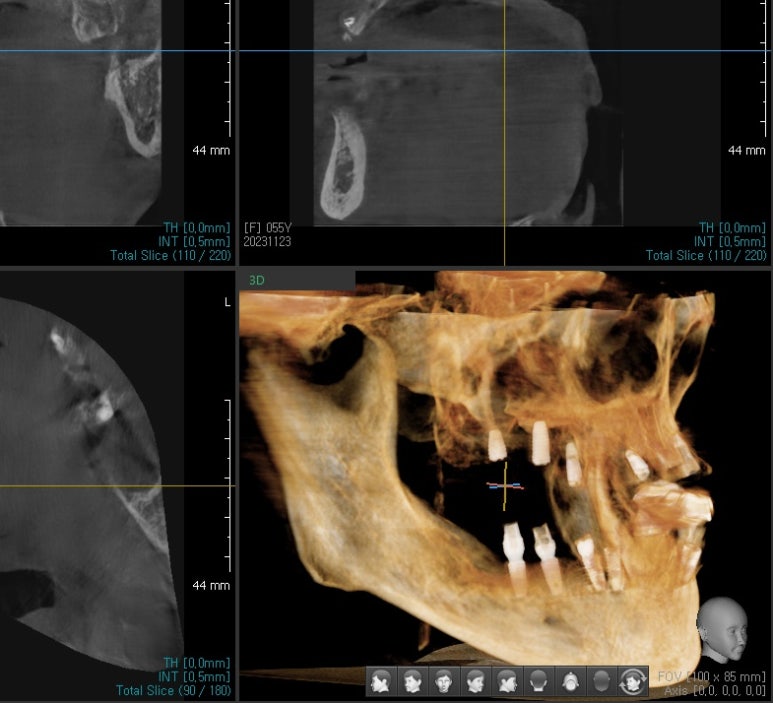

환자 분이 한국에 오신 다음날

계획된 개수 임플란트를 모두 식립하였고

아래쪽 어금니 같은 경우는 임플란트 식립 수술한 바로 다음날임시 치아를 끼워 드려서 씹을 수 있게 해드렸습니다

위 전체 임시틀니, 아래 앞니 임시틀니, 아래 어금니 임시치아 상태

환자 분 의 뼈 상태가 매우 좋으면

다른 부분도 임시 치아를 바로 올릴 수도 있겠으나

환자 분 의 뼈가 매우 약 했기 때문에

환자 분 의 잇몸 뼈 와 임플란트 뿌리 부분이 잘 붙을 때까지

상악부위는 임시 틀니를 해 드렸고

아래쪽 앞뒤 같은 경우도 뺐다 꼈다 하는 임시 치아를 만들어 들었습니다

임플란트가 잇몸뼈와 충분히 유착될때까지 3개월 정도 기다렸다가

다시 한국에 오셔서 저희 치과에서 인플란트 머리까지 완성 하셨습니다.

전체 임플란트 치료 후 모습

지금까지 전체 인플란트를 하기 위해 홍콩에서 저희 시청역 연세 예감 치과를 찾아 주셔서

상담 후에 윗니 전체 임플란트, 아랫니 오른쪽 어금니임플랜트, 아래쪽 앞니 임플란트 등

한 번에 많은 임플란트 수술을 하신 환자 분 의 케이스였습니다.